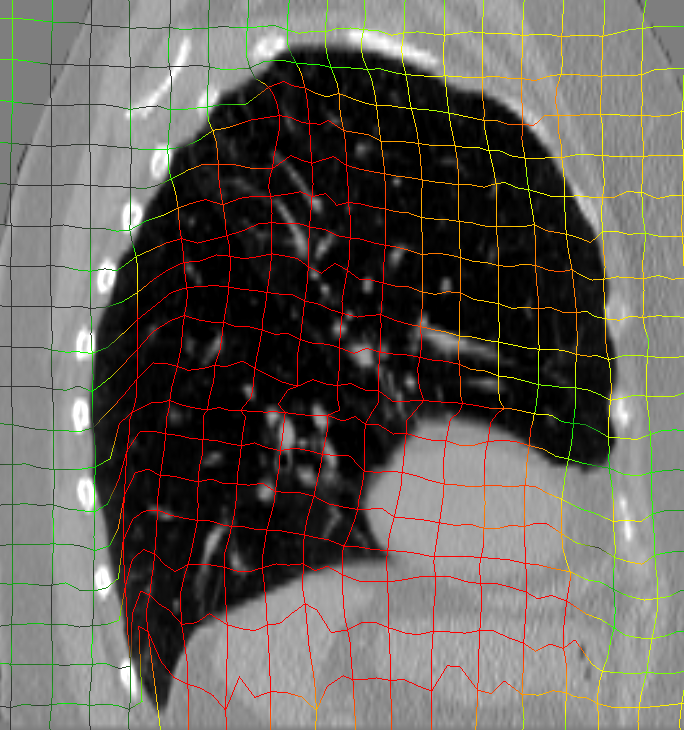

Analysis of the DVF with respect to anatomically implausible deformations showed that the FoF per image dataset was on average 0.25 % of the calculated deformation vectors. The average Jacobi determinant value was 1.00 0.32. A deeper inspection of the Jacobi determinant values revealed that folding occurs mainly in the area of large deformations close to the image or patch border where tissue can move out of or into the field of view.

The initial average landmark distance between consecutive phase images was 2.25 1.55 mm for the Popi datasets and 2.19 2.02 mm for the DirLab datasets. The proposed registration algorithm could decrease the average distance to 1.24 0.90 mm and 1.54 1.31 mm, respectively. For a comparison with existing 4D registration methods we applied the publicly available method by [23] to the respiratory datasets and achieved average registration errors similar to the ones of our method: 1.56 1.42 mm for the DirLab and 1.11 0.87 mm for the Popi datasets. The construction of trajectories for voxels requires the combination of all DVF of a 4D dataset. As a consequence the registration error at the start of a trajectory gets propagated over time and increases or decreases with the combination of the different DVF. In Fig. 4 the error evolution is visualised for the three test datasets. At the beginning the mean registration error is 1.54 mm for the DirLab datasets and 1.24 mm for the Popi datasets. The error then increases to a mean of 2.58 mm for DirLab and 2.07 mm for Popi in the middle of the periodic motion. In the end of the breathing cycle the error falls to an error around 1 mm for both datasets. A similar error propagation pattern could be measured for the Sunnybrook datasets. For the Sunnybrook datasets segmentations are only available for the extreme phases, which allows only four comparisons per dataset. When starting with the end-diastolic phase a comparison in the middle of the cyclic motion to the end-systolic segmentation and in the end of the cycle motion to the original end-diastolic segmentation is possible. The same applies when starting with the end-systolic segmentation. In Fig. 4 the red dots indicate the measured DSC overlap, the red dotted line was fitted to the dots and estimates the DSC overlap for phase images without a segmentation available. Compared to a direct registration of the maximum exhale and inhale phases the registration error increased on average by 0.48 mm with the combination of the DVF. The average registration error for the extreme phases in the Popi dataset increased from 1.46 1.59 mm to 1.98 1.56 mm when we registered the whole 4D dataset instead of the two extreme phases solely. The same analysis reported an increase from 1.83 2.35 mm to 2.54 2.01 mm for the DirLab images and and decrease in the DSC from 0.86 0.10 to 0.79 0.14 for the Sunnybrook data. The DVF of the 4D evaluation showed a FoF of 0.02 % and an average Jacobi determinant of 1.00 0.06.

a) DirLab08 deformation grid

for inhale to exhale registration

a) DirLab08 deformation grid

for inhale to exhale registration

b) DirLab08 with overlayed image foldings

(Jacobi determinant 0)

b) DirLab08 with overlayed image foldings

(Jacobi determinant 0)

c) DirLab08 registration error